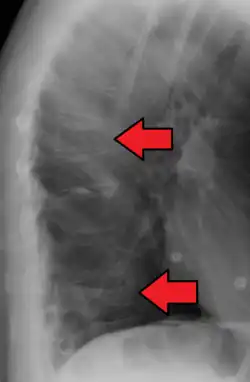

A compression fracture is a collapse of a vertebra. It may be due to trauma or due to a weakening of the vertebra (compare with burst fracture). This weakening is seen in patients with osteoporosis or osteogenesis imperfecta, lytic lesions from metastatic or primary tumors,[1] or infection.[2] In healthy patients, it is most often seen in individuals suffering extreme vertical shocks, such as ejecting from an ejection seat. Seen in lateral views in plain x-ray films, compression fractures of the spine characteristically appear as wedge deformities, with greater loss of height anteriorly than posteriorly and intact pedicles in the anteroposterior view.[3]

Compression fractures are usually diagnosed on spinal radiographs, where a wedge-shaped vertebra may be visible or there may be loss of height of the vertebra. In addition, bone density measurement may be performed to evaluate for osteoporosis. When a tumor is suspected as the underlying cause, or the fracture was caused by severe trauma, CT or MRI scans may be performed.

Compression fracture of the fourth lumbar vertebra post falling from a height. -